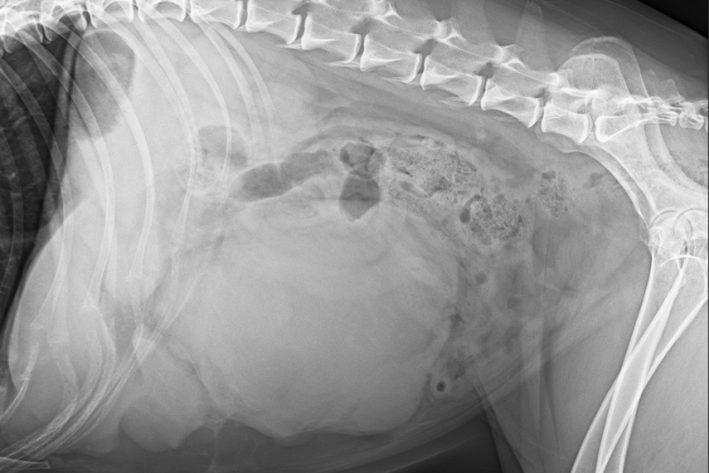

Röntgenaufnahmen der Bauchhöhle zeigen häufig eine Umfangsvermehrung im mittleren oder vorderen Bauchbereich, sowie verminderte Detailerkennbarkeit der einzelnen Organe, welche durch die Blutung in den Bauchraum zustande kommt. Auf Grund der hohen Metastasierungsrate sollte zusätzlich stets die Lunge in mehreren Ebenen geröntgt werden. Selbst bei guter Röntgentechnik muss man jedoch von einem hohen Anteil nicht erkennbarer Metastasen ausgehen. Eine CT- Untersuchung kann den Anteil der erkennbaren Metastasen erhöhen, aber auch diesem Verfahren können ganz kleine Metastasen nicht gesehen werden.

Darstellung eines Milztumors im Röntgen